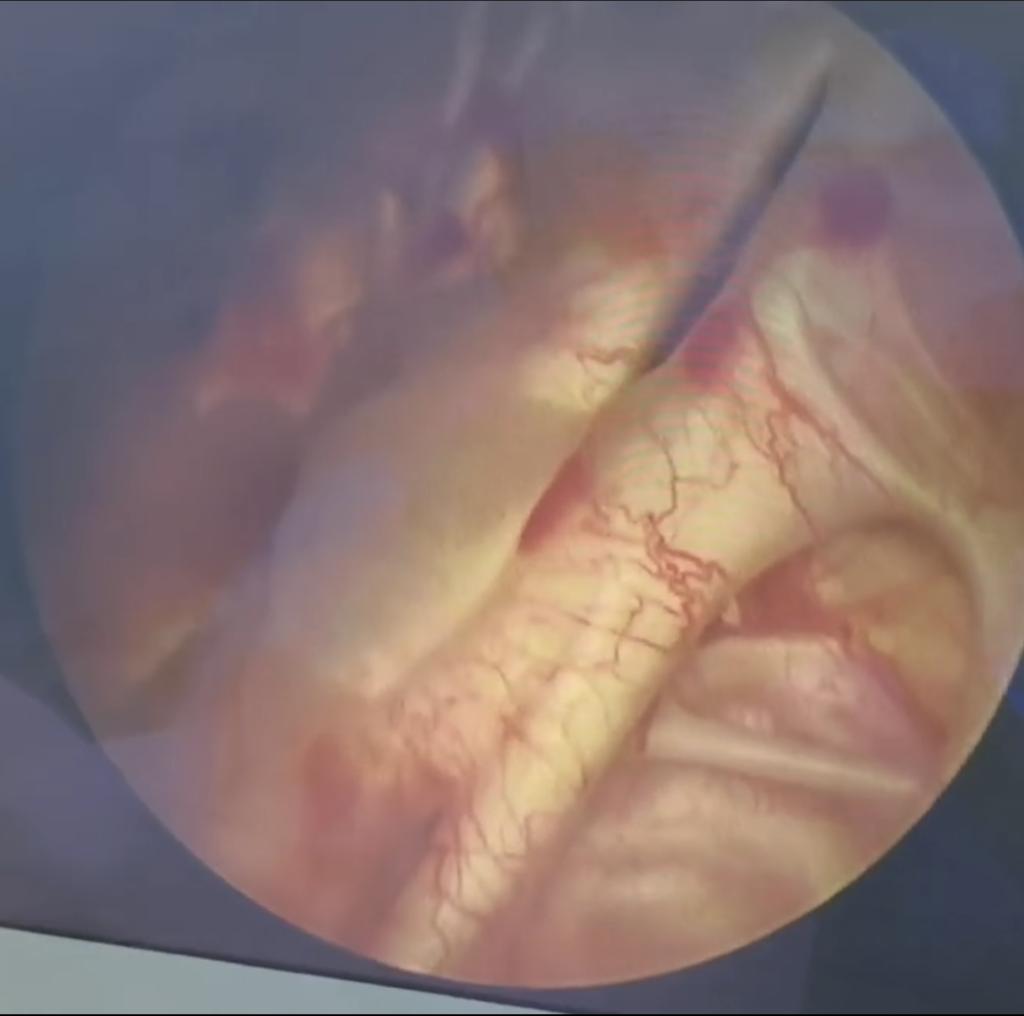

王阿姨膀胱内粘膜

刘主任经验丰富,当看见膀胱内景的第一眼,“腺性膀胱炎”这个诊断就脱口而出。